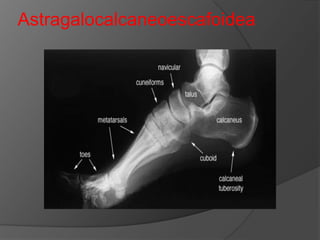

Astragalocalcaneoescafoidea.

Astragalocalcaneoescafoide

a

De tipo enartrosis por delante del tarso.

Carillas calcáneas anterior y media de la

superficie inferior de la cabeza del

astrágalo.

 Carillas anterior y media del astrágalo se

apoyan en la superficie superior del

calcáneo.

 El calcáneo y el escafoide se encuentra

unido mediante el ligamento

calcaneonavicular al que se une el

astrágalo por la superficie inferior de la

cabeza de este.

Astragalocalcaneoescafoidea